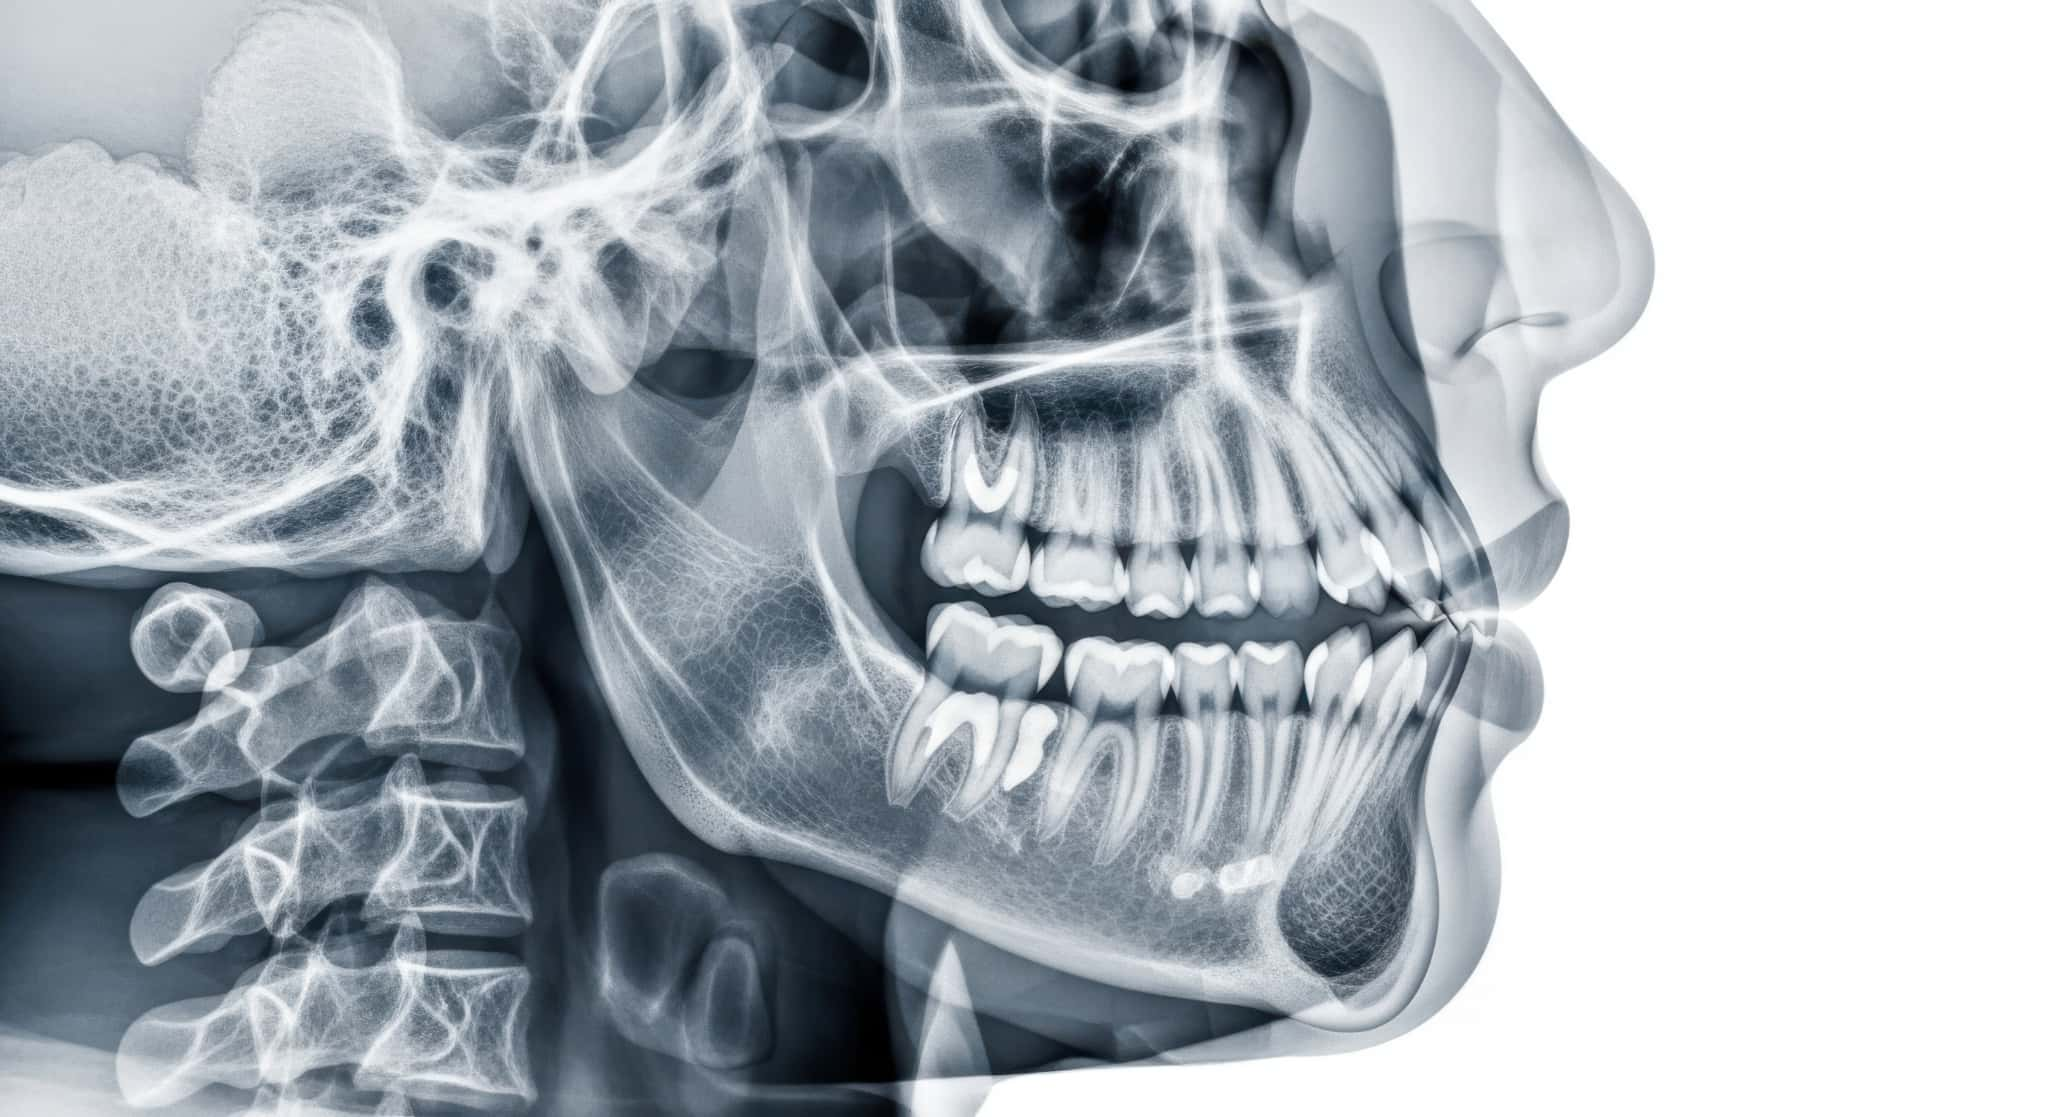

親知らずが生えるためのスペースが不足していることが分かる顎の透過図

親知らずが横向きに生える主な原因は、顎の骨のスペース不足です。現代人は、食生活の変化により硬いものを噛む機会が減少し、顎が小さくなったといわれています。その結果、親知らずが生えるための十分なスペースが確保できず、正しい方向に生えることが難しくなるのです。

また、すでに他の歯が並んでいる状態で生えてくることも原因の一つです。親知らずは成長期が終わった10代後半以降に生え始めるため、限られたスペースに無理やり生えようとして、横向きに埋まったままになることもあります。